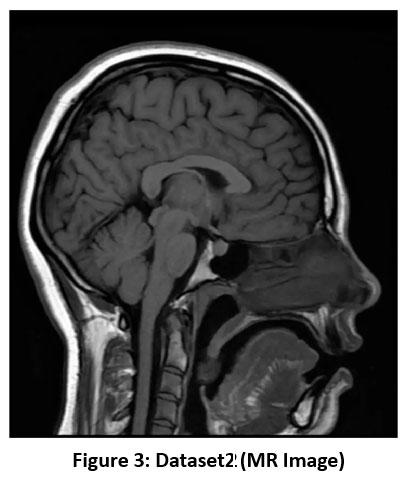

Figure 3: Dataset2 (MR Image) |

The most likely sequence from the current MR imaging scan is the T1-weighted MRI sequence shown in Figure 3. In the T1-weighted picture, the gray matter of the brain is darker compared to the white matter, and the cerebrospinal fluid inside the ventricle is dark, too. This pattern is useful for detailing the architectural diversity of the human brain. It is mainly employed in high-resolution anatomical imaging to attain clear border demarcation between various brain areas.